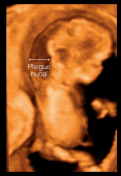

El pliegue nucal

En los últimos 15 años la denominada "ecografía del primer trimestre" ha cobrado mucha importancia, por lo que resulta esencial que acudas a esta prueba y seas consciente de la información que proporciona. Hace años, esta ecografía tenía como objetivos fundamentales comprobar la viabilidad...